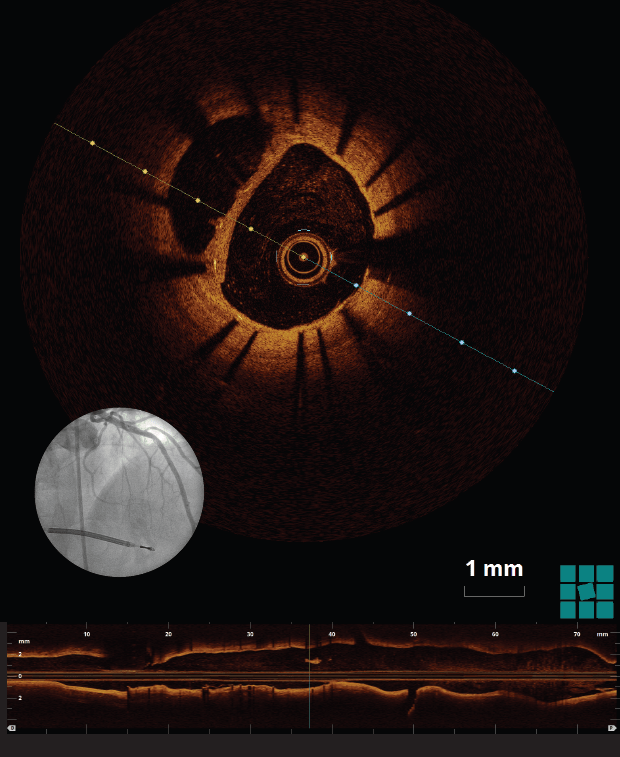

Optical coherence tomography (OCT), a catheter-based invasive imaging system, uses light instead of ultrasound to produce high-resolution, real-time images of coronary arteries and deployed stents for patients with cardiovascular disease. OCT allows cardiologists to see details inside blood vessels that were never seen before, and the resulting images are almost to the level of a microscope in terms of resolution. The visualization can be more than 10 times the detail of intravascular ultrasound.

OCT is useful as a diagnostic tool, offering excellent tissue characterization for plaque components and planning interventions. Therapeutically, this modality facilitates interventions by offering the most precise dimensions for device selection, which optimizes results after stenting by revealing things such as stent expansion and positioning. Biodegradable stents need even more precision in implantation than other types of stents do, and OCT offers that precision. OCT allows doctors to accurately measure luminal architecture and gain insights regarding stent placement and, in the case of biodegradable stents, information about the time it takes for them to dissolve.

Image of Optical coherence tomography